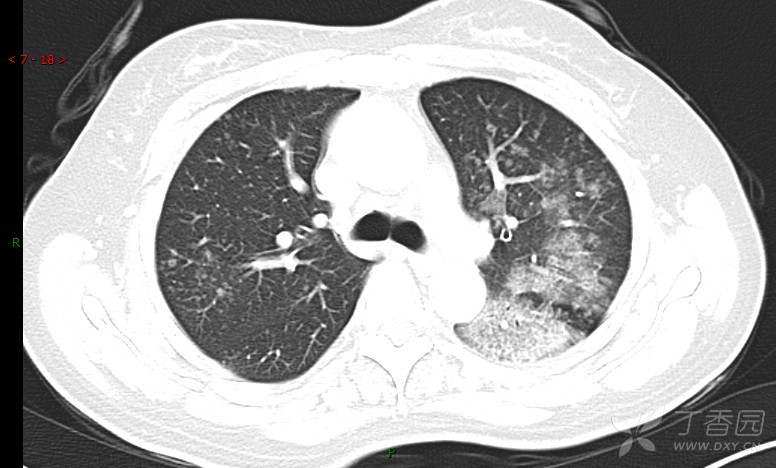

腺泡结节影,蜂窝征,这些都在提示……(病例3连发,附其他2例链接,病理已公布)

咳嗽1年余,加重7天。

患者于1年余前始受凉后出现咳嗽,多为干咳,未在意,未到医院就诊。近3月患者出现咳痰,多为黄色粘痰,量大,伴乏力,偶有头晕、心慌,无发热、胸痛、憋喘,无低热、盗汗、咯血、胸痛,无头痛,无恶心、呕吐、腹痛、腹泻,无尿频、尿急、尿痛,在当地诊所给予抗感染等对症支持治疗(具体药物及剂量不详),症状仍时有反复。患者于1月余前到外院就诊,行胸部CT提示双肺炎症,左肺重,考虑为“间质性肺炎”,给予“左氧氟沙星、利巴韦林、头孢哌酮舒巴坦钠注射液”治疗,复查胸部CT示病灶吸收不理想,后出院继续于诊所对症治疗(具体药物及剂量不详),效果欠佳。7天前患者无明显诱因出现上述症状加重,为求进一步诊治,特来我院就诊,我院门诊以“肺炎(重症)?”收入留观室,留观室给予“盐酸莫西沙星氯化钠”等对症治疗后,今日转入我科。患者自发病以来,神志清,精神差,饮食正常,睡眠增多,大小便正常,体重近3月减轻5公斤余。